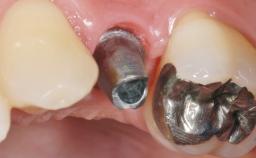

Early Placement of an Implant in a Maxillary Right Central Incisor Site

This 41-year-old female patient was referred to the clinic for the replacement of the right central incisor, since the tooth had developed a root fracture in the long axis that made extraction necessary. The healthy, non-smoking patient was first seen with the tooth still in place. A detailed Esthetic Risk Assessment was performed.The patient was worried about her dental esthetics and had high expectations for a successful treatment outcome from an esthetic point of view. The patient had a medium lip line that displayed parts of the gingiva in the anterior maxilla upon smile.

Defining Characteristics One missing tooth to be replaced by an implant-borne crown

Loading Protocol Conventional or early

Retention Cemented, with prosthesis margin < 3mm submucosal Cemented, with prosthesis margin < 3mm submucosal

Provisional Implant-Supported Prosthesis Prosthodontic margin < 3 mm apical to mucosal margin Prosthodontic margin < 3 mm apical to mucosal margin